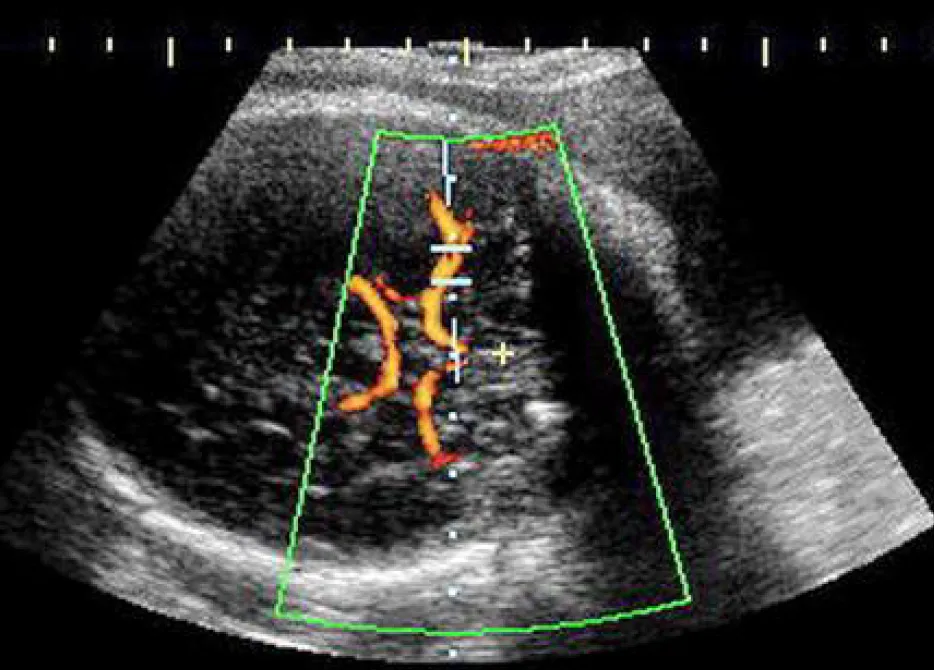

【113-2 醫學(六) 第36題】22歲孕婦,G4P1SA2,妊娠32週,接受杜卜勒(Doppler)超音波檢查,結果如圖所示,檢查名稱為何?

詳解

破題關鍵

這張超音波影像的關鍵在於辨識出胎兒頭部內的血管結構,並結合杜卜勒(Doppler)測量,指向胎兒腦部的動脈血流評估。

選項拆解

-A:錯在臍動脈位於臍帶中,影像中並未顯示臍帶的典型結構,而是胎兒頭部內的血管。